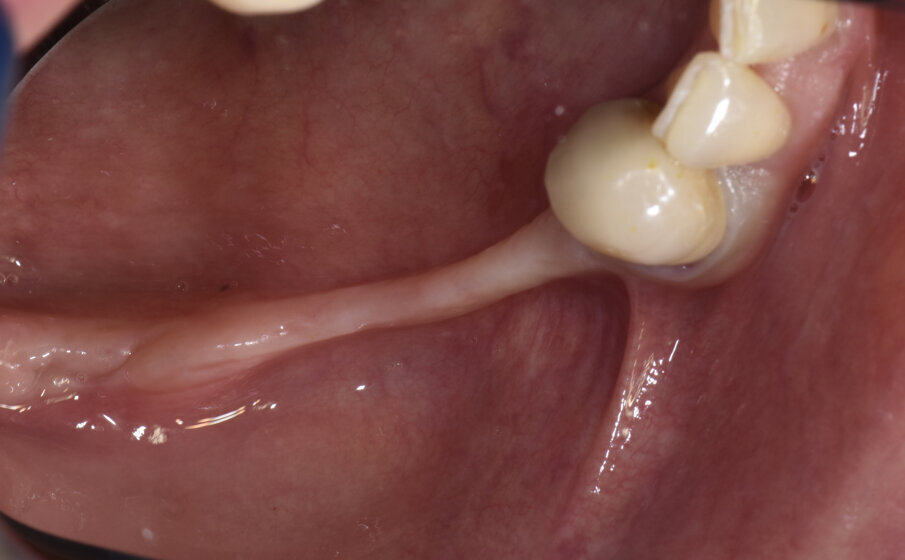

I due impianti (4 x 10 in sede 4.4 e 4 x 8.5 in sede 46 – Nobel Biocare AG – Kloten, Switzerland) sono stati inseriti con modalità sommersa e con un torque di 45 Ncm. Al momento della rimozione della griglia (Fig. 10) non è stata visibile alcuna significativa perdita ossea e il tessuto osseo rigenerato è apparso di notevole consistenza, tanto che alcuni frammenti della periferia della griglia, completamente ricoperti da osso neoformato, sono stati lasciati in situ per evitare rimozione di tessuto osso e perché non interferivano con l’inserimento implantare. L’analisi istomorfometrica del prelievo osseo eseguito con una fresa iniziale cava di 2.5 mm nel futuro sito implantare in posizione 4.4, ha mostrato la presenza di una matrice vitale e densa e senza focolai infiammatori. Durante la fase di riapertura degli impianti, eseguita a gennaio 2019, a causa di una inadeguata banda di mucosa cheratinizzata sul versante vestibolare, è stato eseguito un intervento di vestiboloplastica mediante affondamento di fornice e innesto epitelio-connettivale prelevato dal palato. A distanza di due mesi sono iniziate le fasi protesiche (Fig. 11). Le corone protesiche sono state cementate sui monconi implantari a maggio 2019 ed è stata eseguita una radiografia endorale di controllo (Figg. 12a, 12b). Le fasi protesiche sono state eseguite dal dott. Razzini.

Fig. 11_Vestiboloplastica con innesto epitelio connettivale per aumentare la banda di mucosa cheratinizzata intorno agli impianti.

Figg. 12a, 12b_Immagine clinica e radiografica che mostrano il manufatto protesico finale.